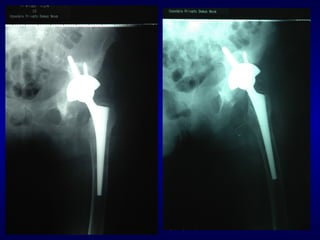

Prof. H.WAGNER

1992

WAGNER CONICAL STEM

WAGNER STEM

1992 - 98

• RIPRESA MOLTO RAPIDA

• PROTOCOLLO POST-OP IDENTICO AI

CASI PRIMARI (CARICO TOTALE A

4 SETTIMANE)

• ECCELLENTE RICOSTRUZIONE OSSEA

(NON INNESTI)

• 62 % di RISULTATI SODDISFACENTI

(HARRIS Score TROPPO SEVERO !!)